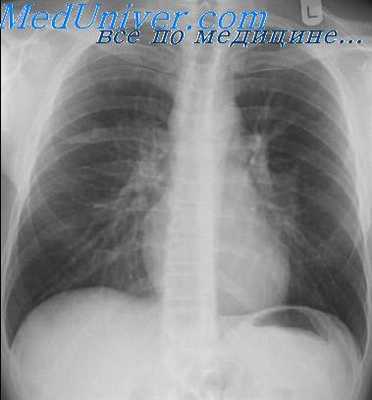

Характерные изменения при саркоидозе выявляются при рентгенографии легких, в ходе КТ или МРТ легких - определяется опухолевидное увеличение лимфоузлов, преимущественно в корне, симптом «кулис» (наложение теней лимфоузлов друг на друга); очаговая диссеминация; фиброз, эмфизема, цирроз легочной ткани. У более половины пациентов с саркаидозом определяется положительная реакция Квейма – появление багрово-красного узелка после внутрикожного введения 0,1—0,2 мл специфического саркоидного антигена (субстрата саркоидной ткани больного).

КТ органов грудной клетки. Множественные типичные саркоидозные очаги субмиллиметрового диапазона с диффузным распространением